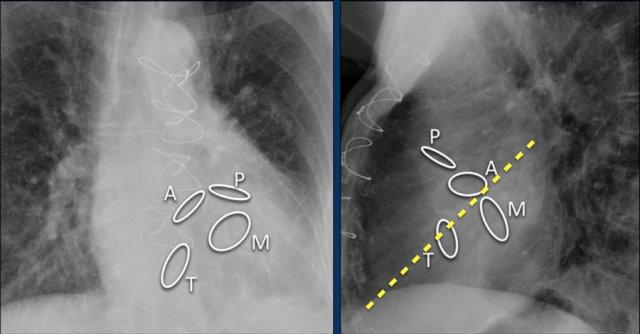

Các hình ảnh cho thấy máy tạo nhịp tim với điện cực nhĩ và điện cực thất.

Đầu điện cực nhĩ hướng lên trên và ra trước, vì vị trí lý tưởng là trong tiểu nhĩ phải, nơi điện cực được neo chặt vào các bè cơ thô.

Đầu điện cực thất được đặt tại mỏm thất phải, vị trí này nằm ở bên trái cột sống trên phim X-quang ngực thẳng và ở phía trước trên phim chụp nghiêng.

Các van tim được xác định rõ nhất trên phim X-quang tư thế nghiêng.

Van động mạch chủ và van động mạch phổi nằm phía trên đường kẻ từ mỏm tim đến nền tim, trong khi van hai lá và van ba lá nằm phía dưới đường này.

Hình ảnh thể hiện vị trí van tim bình thường trên phim X-quang ngực thẳng (PA) và nghiêng.

Trên phim X-quang ngực tư thế nghiêng, van động mạch chủ và van động mạch phổi nằm phía trên đường kẻ từ nền tim đến mỏm tim, còn van ba lá và van hai lá nằm phía dưới đường này.